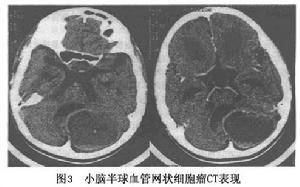

3.CT 典型表現為大囊內有小的瘤結節影,瘤結節和實性腫瘤呈等密度並均一強化,囊壁不強化。實質性腫瘤CT顯示為類圓形高密度影像密度不均勻;囊性者顯示為低密度,較其他囊腫密度高邊緣欠清晰,可見高密度結節突向囊腔內增強後囊壁密度多無變化,瘤結節呈均勻增強。腫瘤周圍可見低密度水腫帶。有人根據CT表現將之分為囊腫結節型、囊腫型、實體型及腦積水四型。